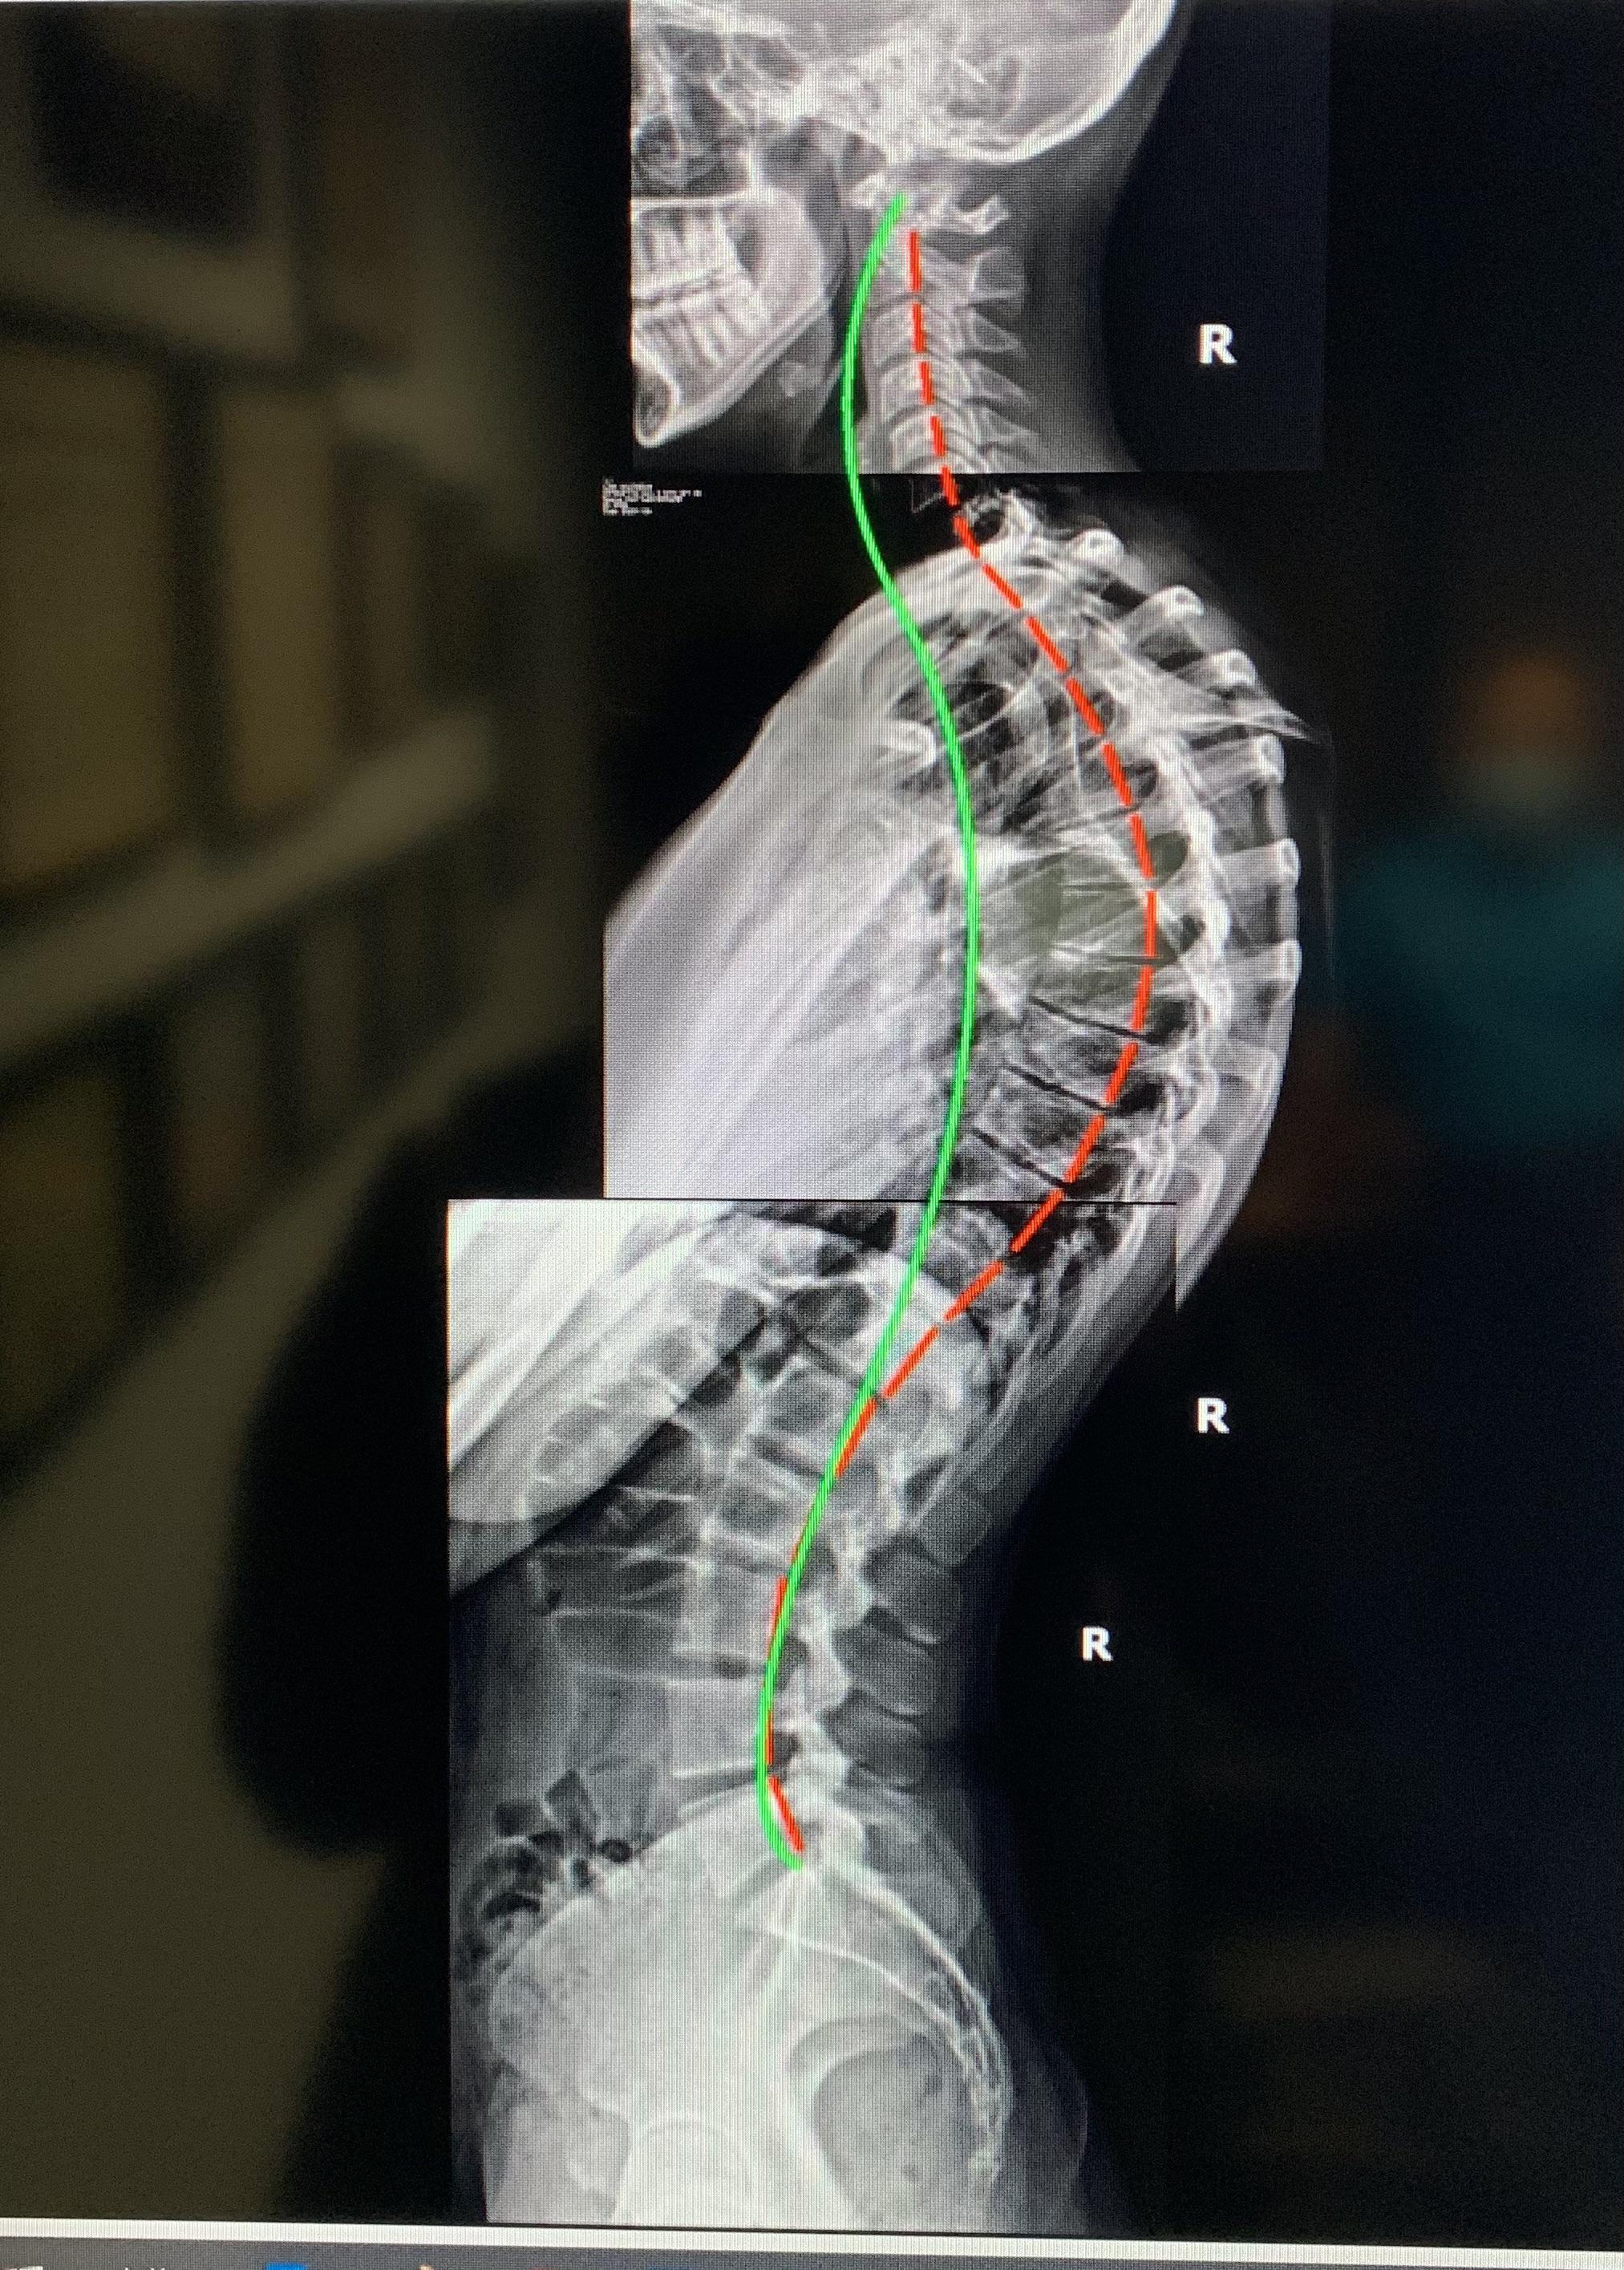

From www.researchgate.net

Cervical kyphosis before and after chiropractic adjustment. A, Sagittal... Download Scientific Kyphosis Chiropractic Nick araza, a chiropractic wellness practitioner at santa barbara family chiropractic, recommends. If your kyphosis is due to trauma or other issues,. Spinal adjustment might be an option for improving spinal movement and curvature. Spinal or chiropractic adjustments are techniques chiropractors perform using their hands or instruments to apply controlled, sudden forces to the spinal joints. Chiropractic can often help. Kyphosis Chiropractic.

So this chiropractor took some xrays and said he can fix me...I need advice. r/kyphosis Kyphosis Chiropractic Chiropractic can often help resolve kyphosis that is caused by poor posture. One of the best ways to treat all kinds of kyphosis, especially kyphosis caused by poor posture is chiropractic care. Spinal or chiropractic adjustments are techniques chiropractors perform using their hands or instruments to apply controlled, sudden forces to the spinal joints. The most common surgery for treating. Kyphosis Chiropractic.